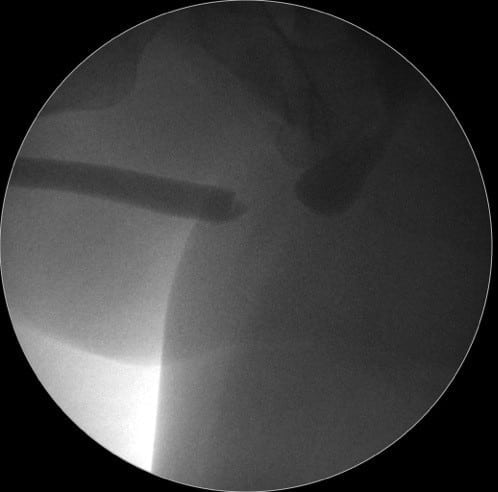

Dr. Marcel Rad – Când evaluăm strictura de uretră ce vedem? Vedem un canal, vedem în uretrografie o zonă de gâtuire, de stenozare a canalului, dar nu vedem şi nu putem să ne dăm seama, indiferent de cât ne chinuim să evaluăm cu ecografie, cu RMN, nu putem să evaluăm corect zona de fibroză, zona de ţesut cicatricial.